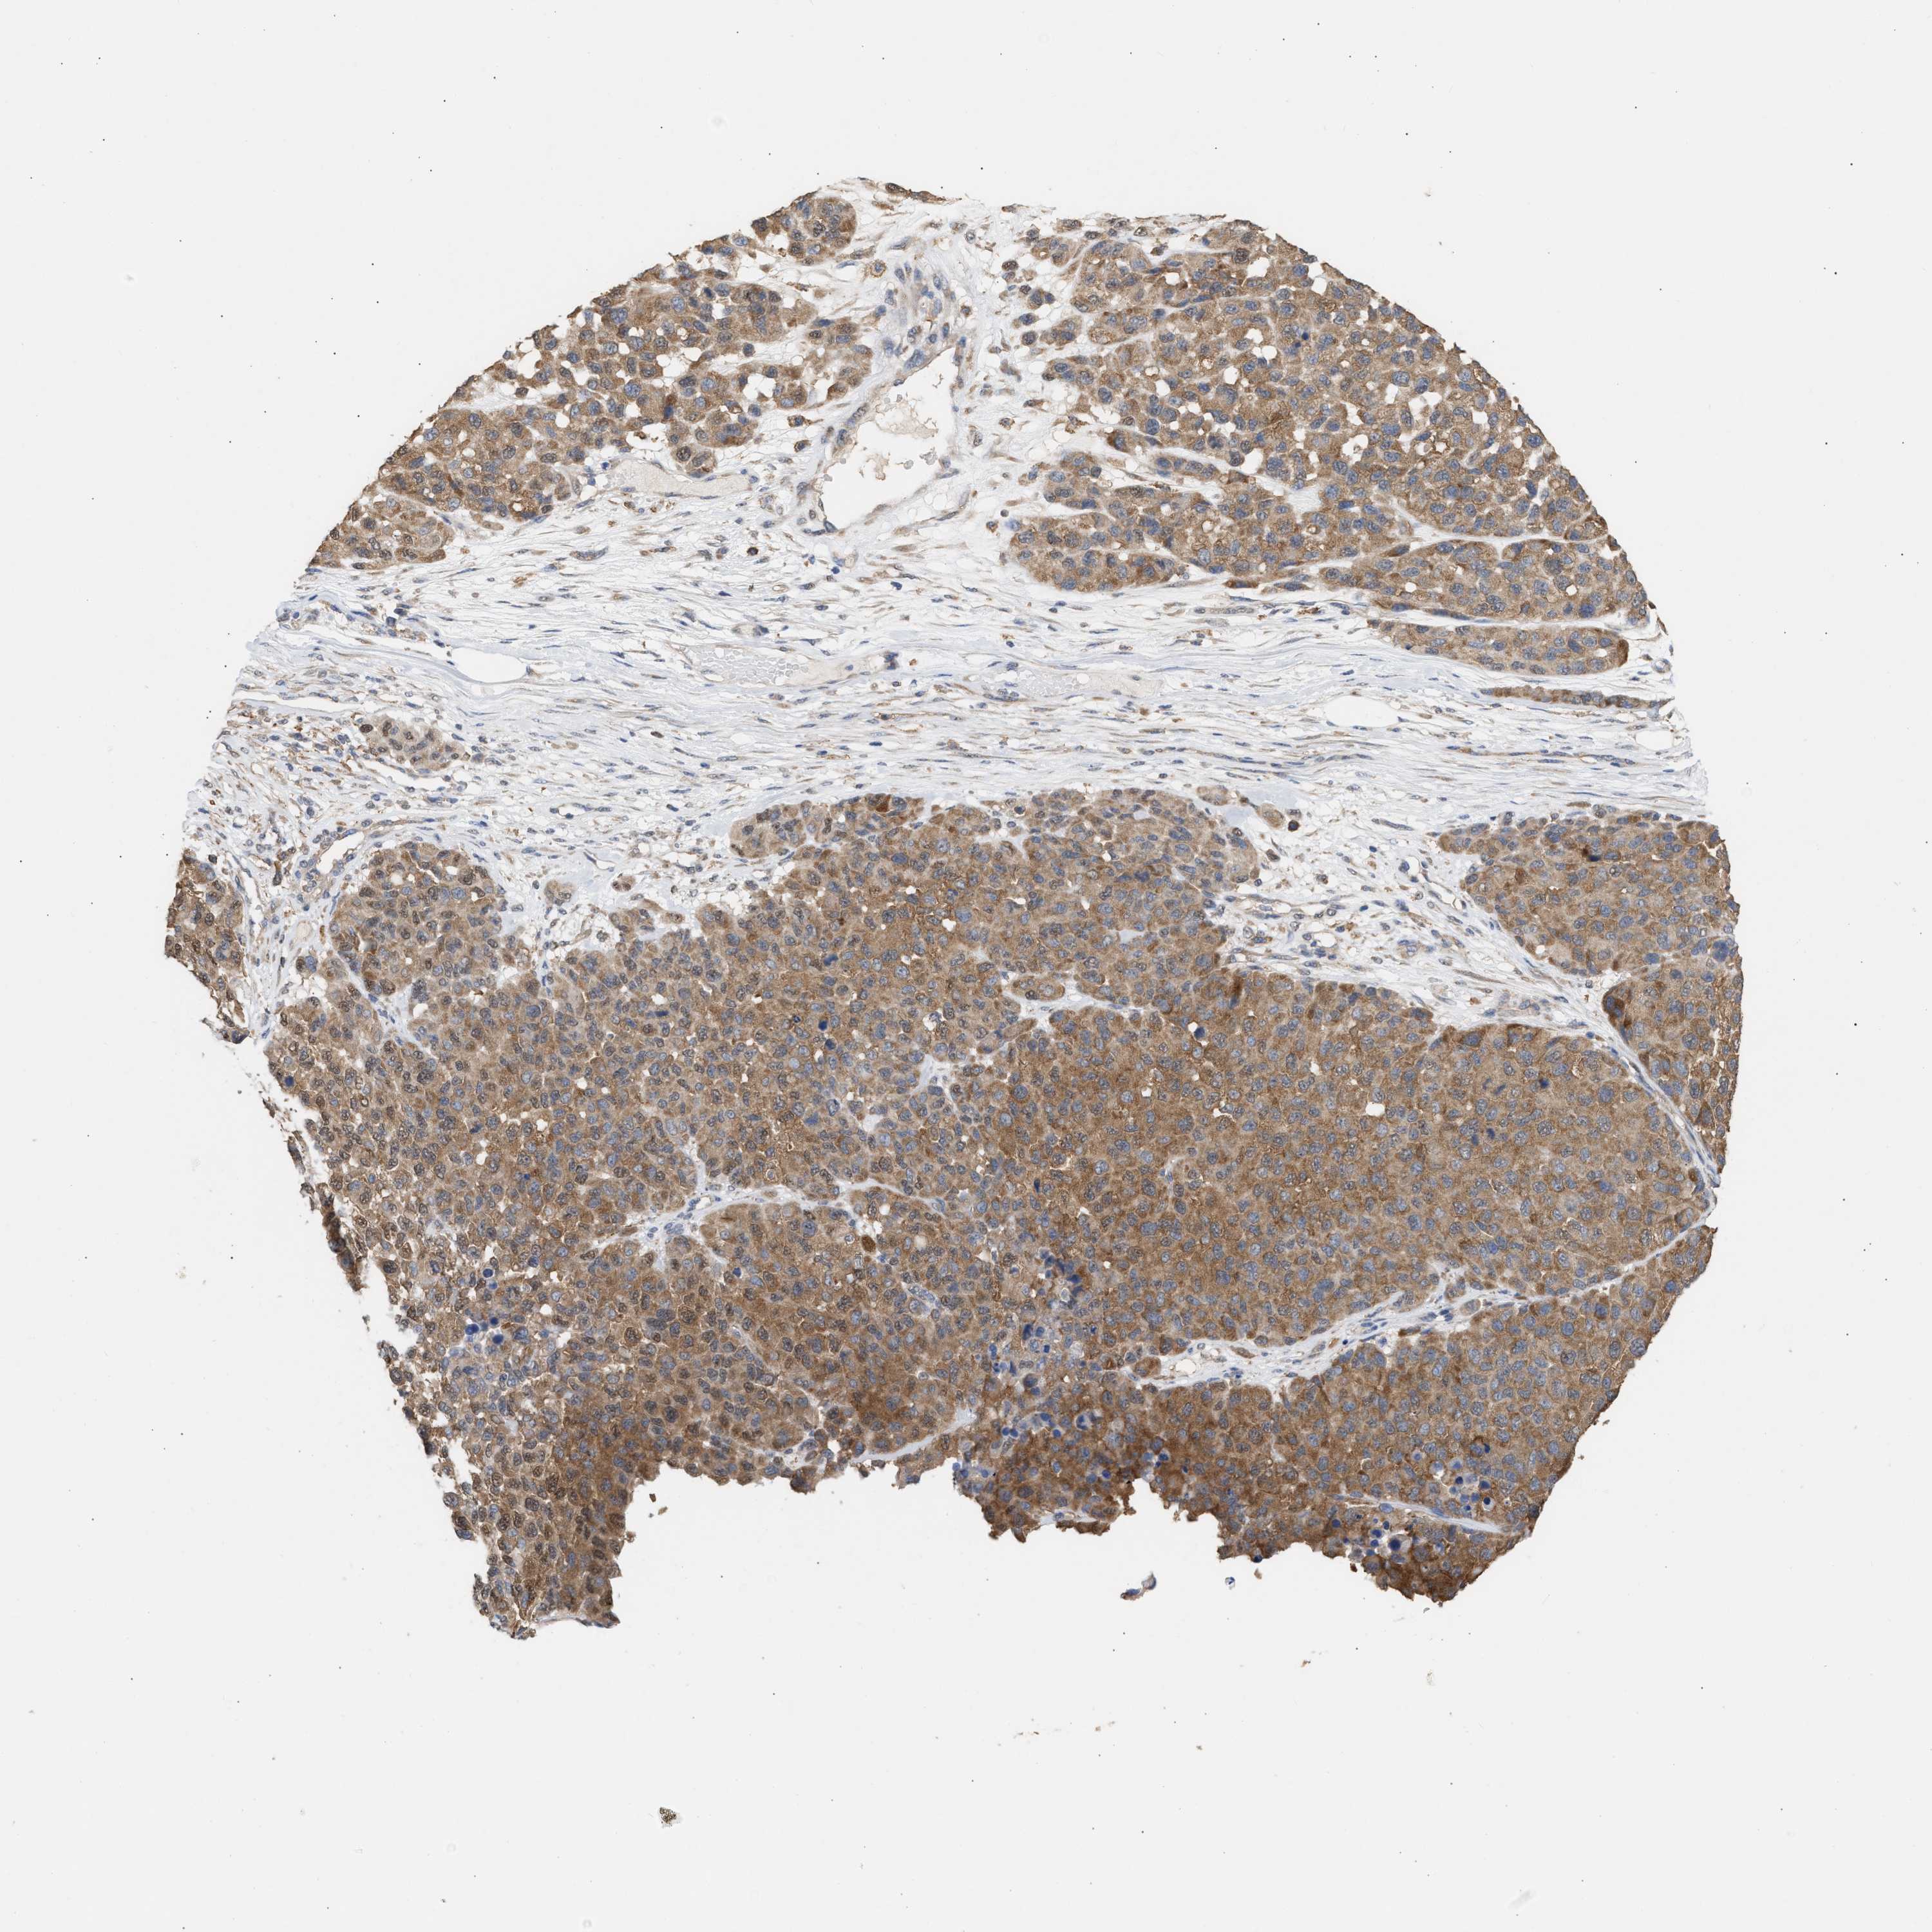

MELANOMA - Protein expressioni

A mouse-over function shows sample information and annotation data. Click on an image to view it in a full screen mode. Samples can be filtered based on level of antibody staining by selecting one or several of the following categories: high, medium, low and not detected. The assay and annotation is described here.

Note that samples used for immunohistochemistry by the Human Protein Atlas do not correspond to samples in the TCGA dataset.

Antibody stainingi

Antibody staining in the annotated cell types in the current human tissue is reported as not detected, low, medium, or high, based on conventional immunohistochemistry profiling in selected tissues. This score is based on the combination of the staining intensity and fraction of stained cells.

Each image is clickable and will lead to virtual microscopy that enables deeper exploration of all samples and also displays staining intensity scores, fraction scores and subcellular localization as well as patient and tissue information for each sample.

Antibody HPA018799

Antibody HPA019648

Antibody HPA024367

Staining

High

Medium

Low

Not detected

Intensity

Strong

Moderate

Weak

Negative

Quantity

>75%

75%-25%

<25%

None

Location

Nuclear

Cytoplasmic/membranous

Cytoplasmic/membranous,nuclear

Malignant melanoma, NOS

Malignant melanoma, Metastatic site